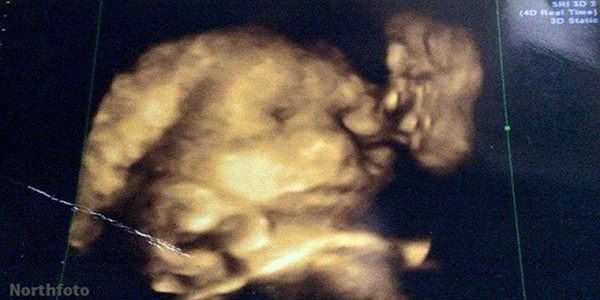

Ya sea un fantasma, una aparición, una alucinación, o incluso sólo un poco de líquido amniótico, una mujer ha visto lo que ella cree que es su abuelo muerto besando a su hijo por nacer en una impresionante ecografía 4D que ha sorprendido al mundo entero.

Jade Hornsby acudió junto a su madre a un centro especializado para realizar el control prenatal correspondiente a sus 30 semanas de embarazo y cuando vieron un extraño rostro en la imagen quedaron impactadas de inmediato.

"Los labios están en una posición como si estuviera haciendo ‘pucheros’ o a punto de dar un beso en la mejilla. Se pueden ver los ojos, la nariz y la boca con tanta claridad”, manifestó la madre que asegura que la extraña imagen es el rostro de Jack Hornsby, su difunto esposo.

Para ser justos con la mamá de esta gestante, la supuesta cara que aparece en la imagen se ve algo ‘arrugada’, como la de un adulto mayor. Aunque el hecho no pasa de ser una simple curiosidad, para Jade representa una bendición de su padre hacia su hija Lacey-Mae que nació sin complicaciones 12 semanas después.